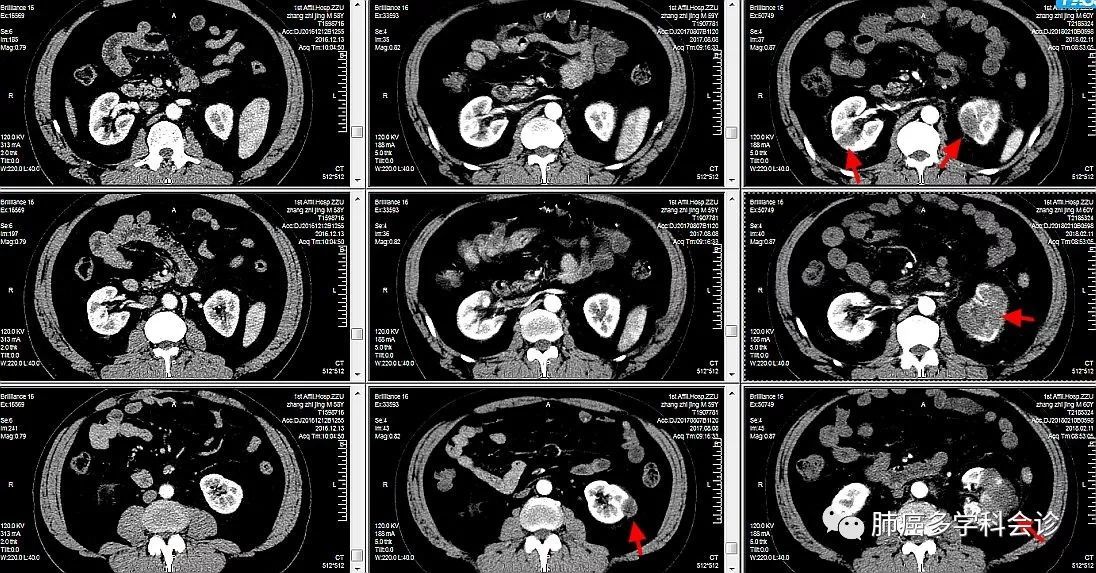

图11-4-2a 右肾癌复发淋巴结转移

图片尺寸951x726